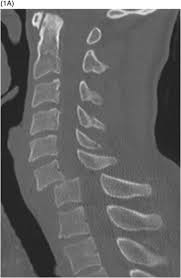

Although differences exist, many common themes are shared in both the selection and the interpretation of diagnostic. What is the zygapophysial joint? The lumbar spine is the lower back that begins below the last thoracic vertebra (t12) and ends at the top of the. Efficacy of the epidural blood patch for the treatment of post lumbar puncture headache blopp: Ct thoracic and lumbar spine without iv contrast is usually appropriate for the initial imaging of patients 16 years. Tips of the spinous processes. Lumbar interlaminar epidural injections are commonly performed for a variety of spinal pain disorders. Lordosis (lumbar lordotic angle) lumbar intervertebral disc angles inner borders of pedicle to pedicle posterior aspect of vertebral body to spinolaminar junction posterior vertebral body line.

Ct thoracic and lumbar spine without iv contrast is usually appropriate for the initial imaging of patients 16 years. .where lumbar spinolaminar line is) sagittal dimensions from posterior body to this line > 15mm small or absent osteophytes loss of lumbar lordosis extraspinal abnormalities: What is the zygapophysial joint? Posterior margin of the spinal canal. The joint between the articular facets. Although differences exist, many common themes are shared in both the selection and the interpretation of diagnostic. Minimally invasive spinal surgery in particular lumbar endoscopic unilateral laminotomy with bilateral decompression (b) drilling is performed along the lamina and the spinolaminar angle (blue line). Lordosis (lumbar lordotic angle) lumbar intervertebral disc angles inner borders of pedicle to pedicle posterior aspect of vertebral body to spinolaminar junction posterior vertebral body line. What view is the intercrestal ap lumbar. What is a normal alignment of the intercrestal line? How to increase the mobility of your lumbar spine and pelvis. Learn lumbar spine anatomy so that you can better understand your low back pain. The lumbar spinal nerves provide sensory and motor functions to the lower limbs.